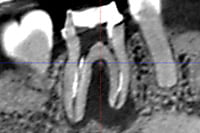

また、レントゲン写真だけでは、歯茎の腫れの原因になっている病巣が見えない事があります。しかし、CTを使えばレントゲン写真では見えなかったむし歯や膿などの病巣をはっきり確認できるケースがあり、原因となっている歯の特定、歯の破折の有無、歯の周りの骨の吸収の有無、歯の神経が通っている根管の形態など、CT画像からはレントゲン画像からは得られにくい様々な情報を得ることができます。もはや、医科と同様、歯科領域でもCT無しでの診断はあり得ない時代になっています。

それは、CT画像を用いた根管の通り道の分析と歯科用顕微鏡を使った根管治療です。

再根管治療では、根管に潜むバイ菌を殺菌・消毒することが特に重要になりますが、根管は三次元的に湾曲していたり、複雑に枝分かれしていたりしていて、実際に根管を殺菌・消毒することは困難を極めることも多いです。再根管治療前に、根管の状態を事前に把握できれば、治療時に注意しなければいけないポイントがわかり、それを治療に反映できるのですが、レントゲン画像では二次元的な画像しか得られないので、根管の走行の把握が足りずに治療の一部が経験や勘の治療になってしまいます。CT画像では根管の三次元的な画像が得られ、レントゲン画像より詳しく根管の状態を把握でき、根管の湾曲具合や未治療の根管の見落としなど、どこを注意しなければいけないかがわかり、勘の治療をせずにすみます。より根管を確実に殺菌・消毒するためには、根管のCTスキャンが有効なのです。

診断に関しては、歯根破折は肉眼や拡大鏡、レントゲン画像ではわかりづらく、CT画像と歯科用顕微鏡を組み合わせて診断するのが有効です。

一見、レントゲン画像ではわかりづらくても、CT画像だと特有の歯槽骨の吸収画像が見られ、確定ではありませんが歯根破折を予測する事ができます。そして、破折が予想されるところを顕微鏡を使用して強拡大で視認することにより、歯根破折を確定診断することができます。